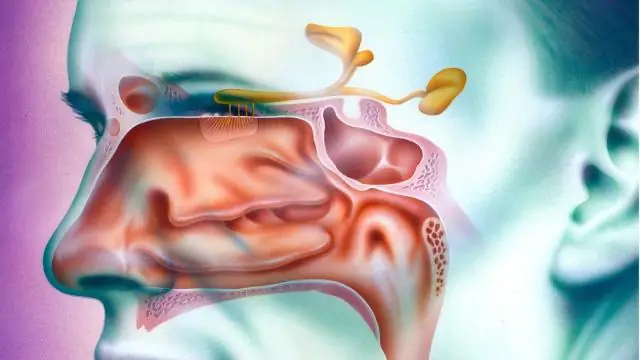

В этом новом эксперименте исследователи внимательно следили за движениями и поведением 32 свободно живущих буревестников Скополи у побережья Менорки. Птицы были разделены на три группы: одна временно подвергалась аносмии (отсутствию обоняния) посредством промывания носа сульфатом цинка; другой несет маленькие магниты; и контрольная группа. Миниатюрные GPS-логгеры были прикреплены к птицам, когда они гнездились и высиживали яйца в расщелинах и пещерах на скалистом побережье Менорки. Но вместо того, чтобы быть перемещенными, их отслеживали, когда они совершали естественные походы за пищей.

Их ориентация улучшилась при приближении к суше, что говорит о том, что птицы должны сверяться с обонятельной картой, когда земля находится вне поля зрения, но впоследствии они могут найти дом, используя знакомые особенности ландшафта.